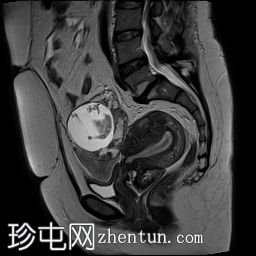

矢状位

T2加权像

可见子宫外腹腔内妊娠囊,内含胎儿组织。

该妊娠囊向后推移子宫,并与剖宫产瘢痕凹陷处紧密相连。

该妊娠囊与相关肠袢无法分离。可见其与性腺血管密不可分,且性腺血管明显突出。

胎盘位于妊娠囊后方,紧贴子宫前壁。

沿妊娠囊下缘可见一处异质性局灶性积液,最大轴向尺寸约为 8.4 × 5.5 cm,T1 加权像呈异质性高信号,T2 加权像呈异质性中等信号,T1 脂肪抑制序列未见信号下降,提示为血液成分。该积液压迫膀胱。

可见周围脂肪间隙呈条索状改变。

左侧卵巢无法辨认。

右侧卵巢未见实性或囊性肿块。

子宫体积增大,后倾,子宫内膜厚度约 1 cm,子宫下段前壁可见局灶性变薄(既往子宫瘢痕)。子宫连接区完整,未见肌层肿块。可见子宫内膜腔边缘有血性分泌物。